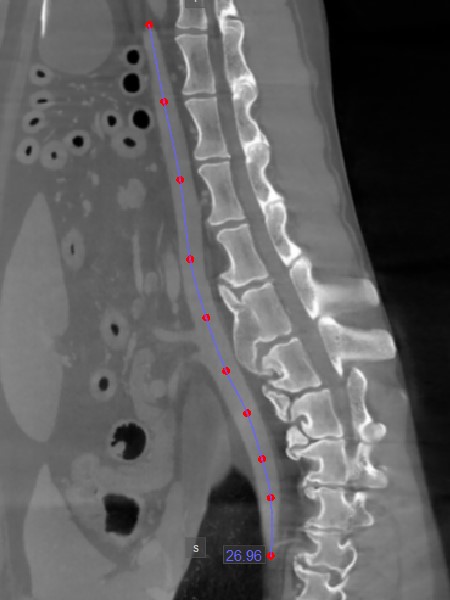

Distance¶

Use the Distance measurement tool to precisely measure the distance between two points with precision.

Select the Distance tool and assign it to one of the available mouse buttons. To calculate the distance, place two points on the active image slice by pressing on the appropriate position with the mouse. The distance

between the two points will be automatically calculated. This tool is assigned to the middle mouse scroll button by default.

Modify the start and end point by using the Default tool from the left toolbar. The distance between the points will be automatically recalculated.